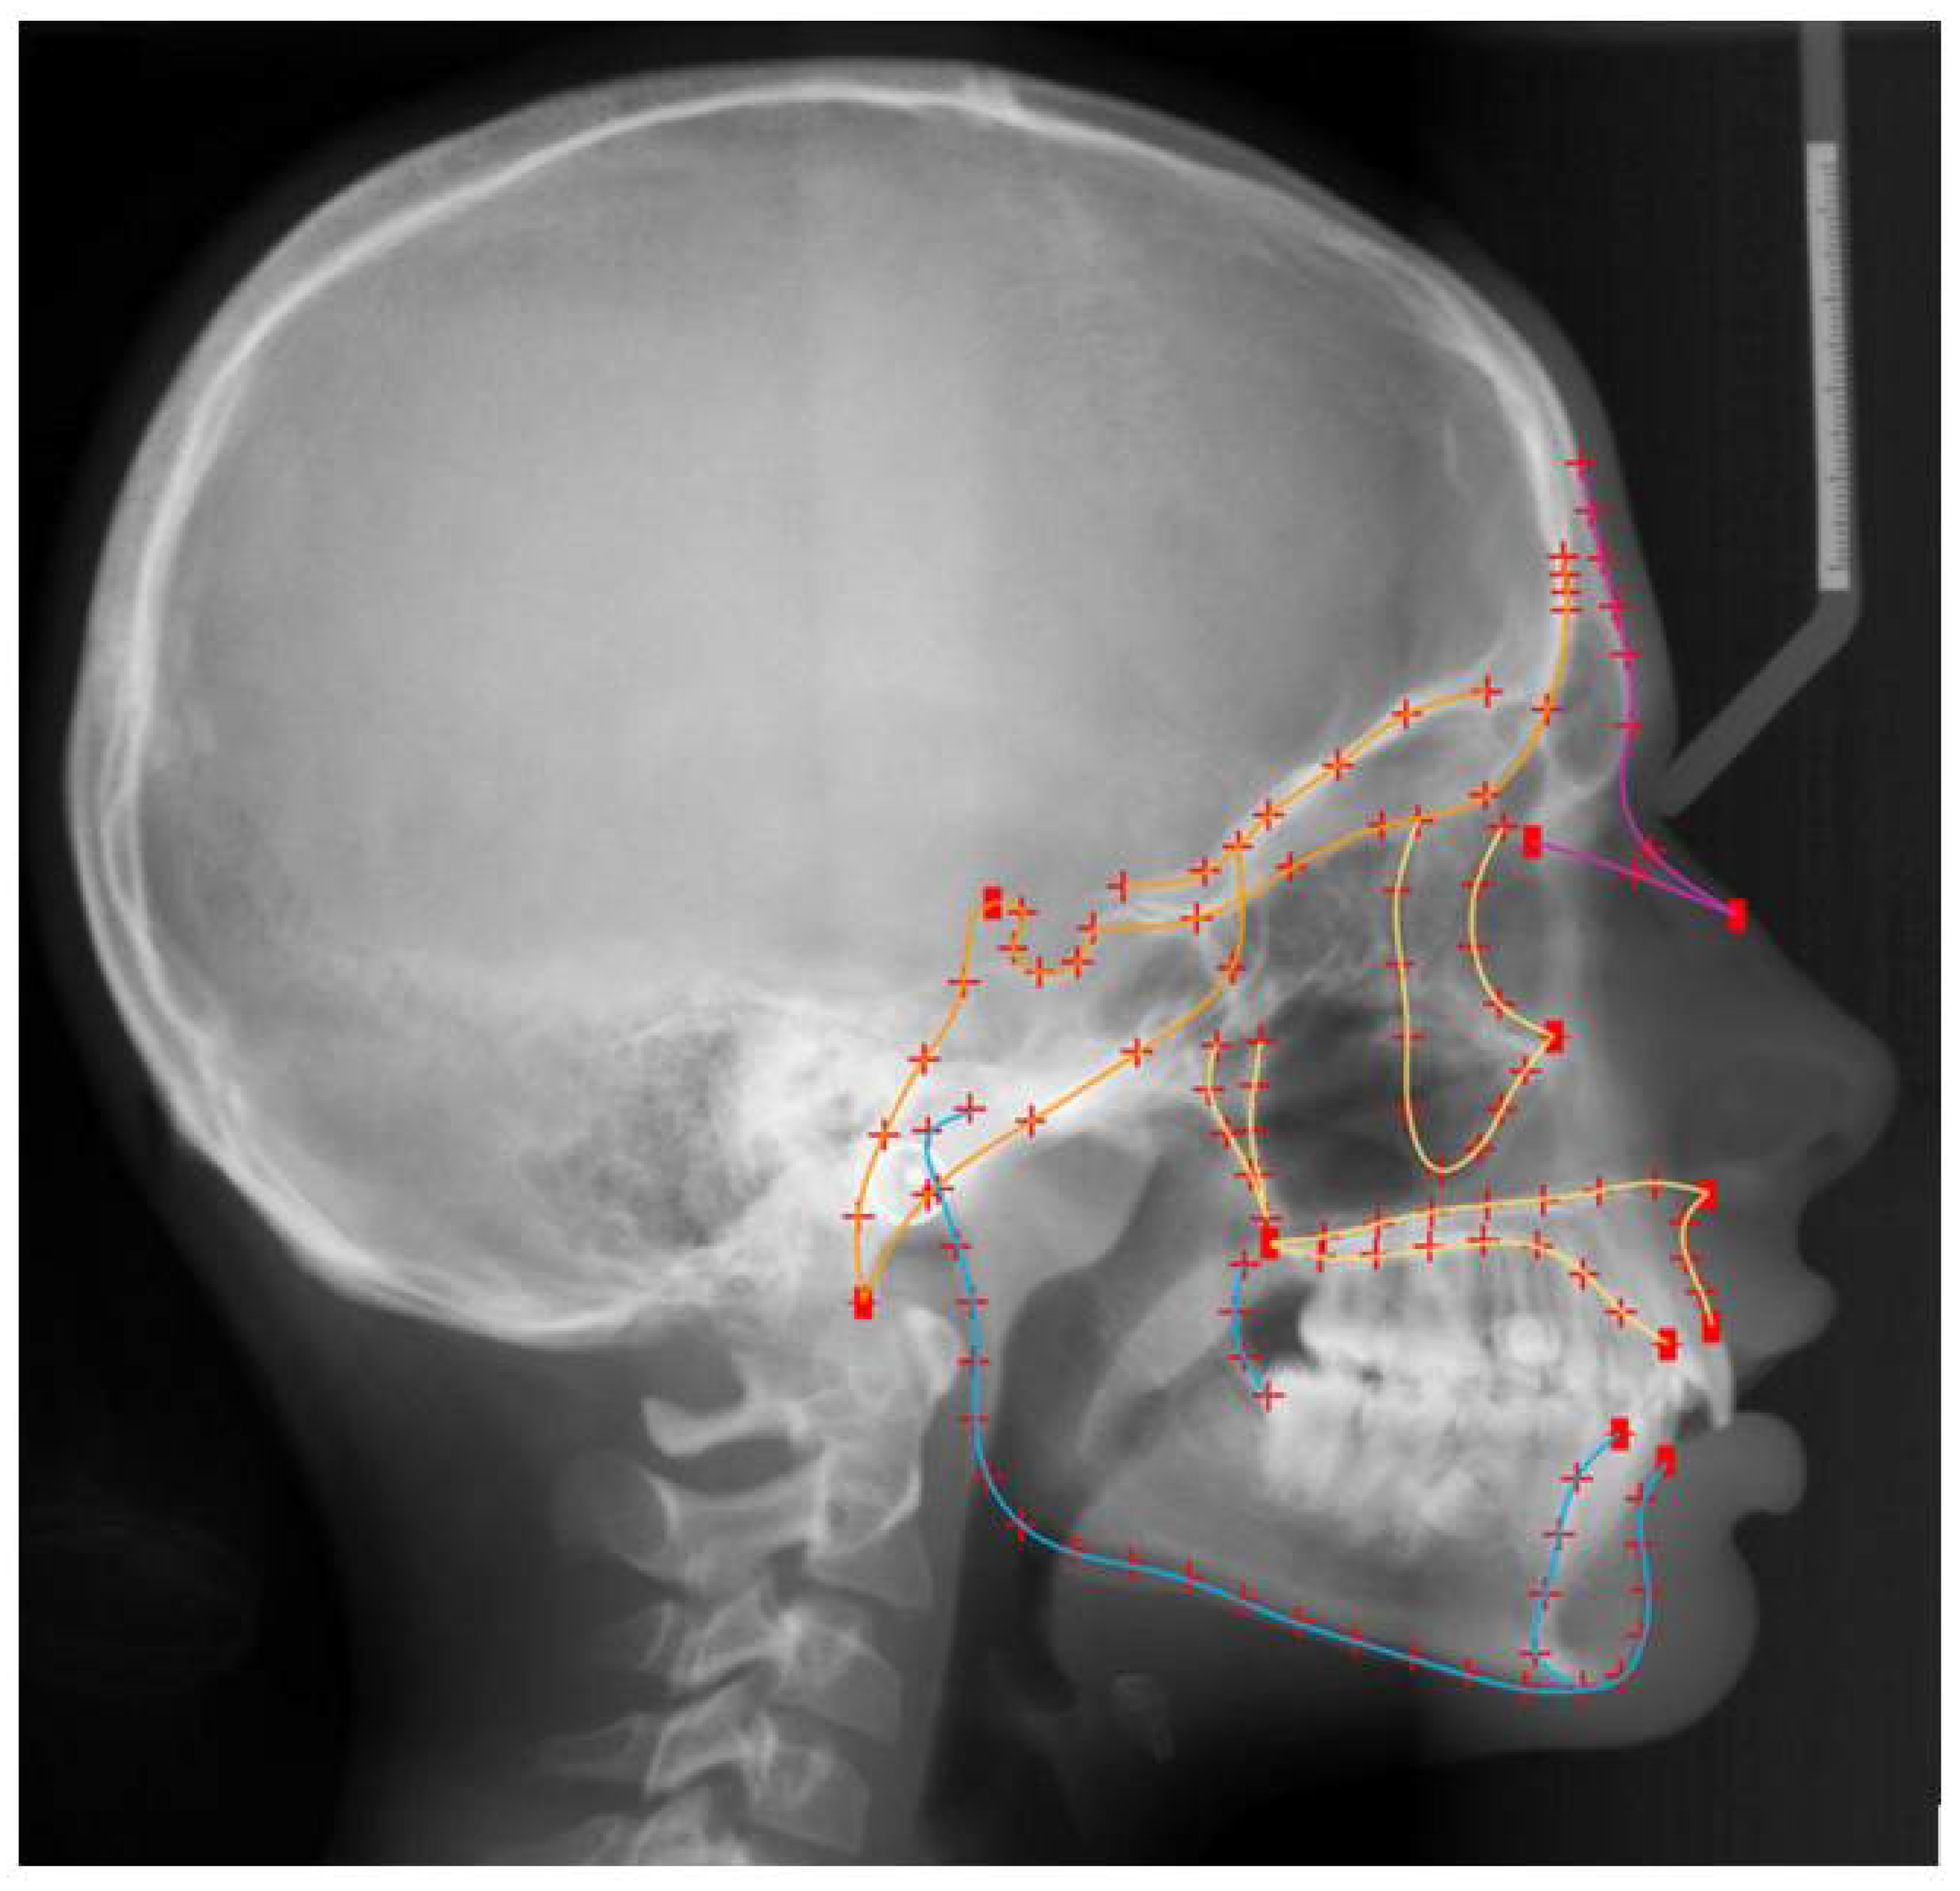

2.3. Shape Assessment

- Halazonetis, D.J. Morphometrics for cephalometric diagnosis. Am. J. Orthod. Dentofac. Orthop. 2004, 125, 571–581. [Google Scholar] [CrossRef]